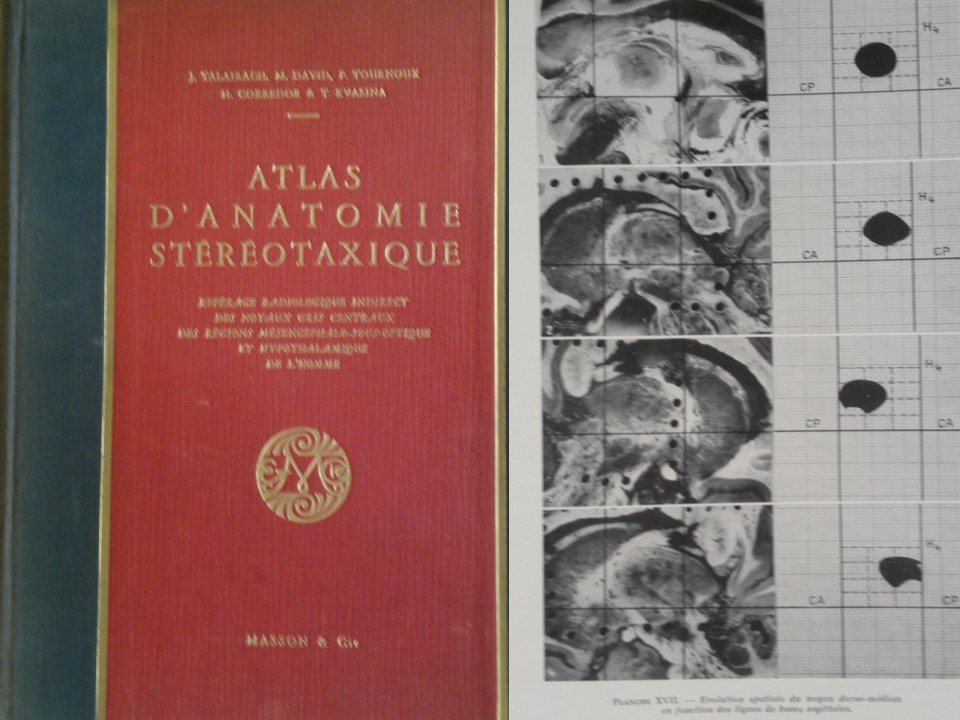

Metodología Estereotáctica o Estereotaxia

Dr. Guillermo Larrarte